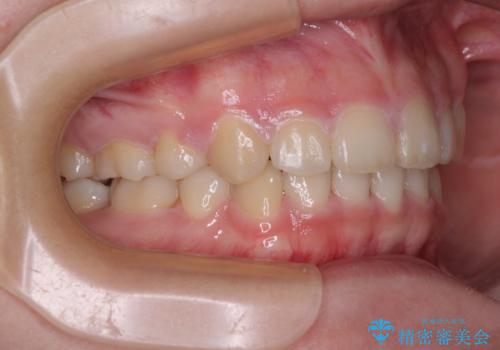

- 口元の閉じにくさを気にして来院された患者様です。

地元で矯正治療を始める予定で上顎左右第1小臼歯2本を抜歯したものの、その後転居したため治療が滞っているとのことでした。

上下ともに歯列が前方に突出していたため、上下左右の第一小臼歯4本を抜去する方針(既に上顎は抜歯されています)で、ワイヤー装置による矯正治療を行うこととしました。